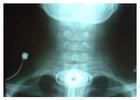

喉鏡檢查可見喉部有瘢痕組織,呈帶狀、膜狀或環狀,聲帶固定不動,室帶、聲帶變形,聲門變狹窄,聲門下區粘連成塊,有時僅留小孔隙。診斷 喉狹窄的發生和發展很緩慢,結合病史和喉側位X線拍片,可作出診斷,並能了解喉狹窄的部位、範圍和程度。